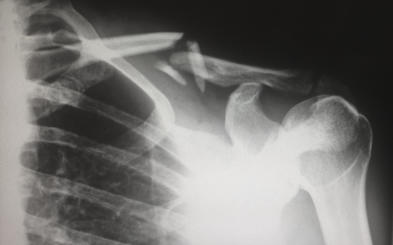

X-rays (radiographs) are the most common and widely available diagnostic imaging technique. Even if you just complain about a sprain in your wrist or ankle, your doctor will probably order radiographs to make sure that no bone is broken. X-rays are always used for fractures and joint dislocations, and may also be recommended if your doctor suspects damage to a bone or joint from other conditions such as arthritis or osteonecrosis (bone cell death). The part of your body being pictured is positioned between the X-ray machine and photographic film. As you hold still, the machine briefly sends electromagnetic waves (radiation) through your body. This exposes the film, creating a picture of your internal structure. The level of radiation exposure from X-rays is minimal, but your doctor will take special precautions if you are pregnant. Bones, tumors and other dense matter appear white or light because they absorb the radiation. Soft tissues and breaks in bone let radiation pass through, making these parts look darker. Sometimes, to make certain organs stand out in the picture, you are asked to drink barium sulfate or be injected with a dye. Several X-rays from different angles may be needed. If you have a fracture in one limb, your doctor may want a comparison X-ray of your uninjured limb. Your X-ray session will probably take 10 to 15 minutes; no specific preparations are required. Each Division of Southeastern Orthopaedic Specialists, P.A. is equipped with state of the art X-ray equipment and facilities. Our facilities utilize high tech digital technology as well as traditional film technology for special views. Our offices have the capability to send your X-ray electronically (and privately) to your physician’s work station or to your exam room. We can also instantly send your “digital films” to those physicians whom might assist you doctor in their interpretation, such as at the hospital or in private practice. But be assured that you confidentiality is maintained at all times.